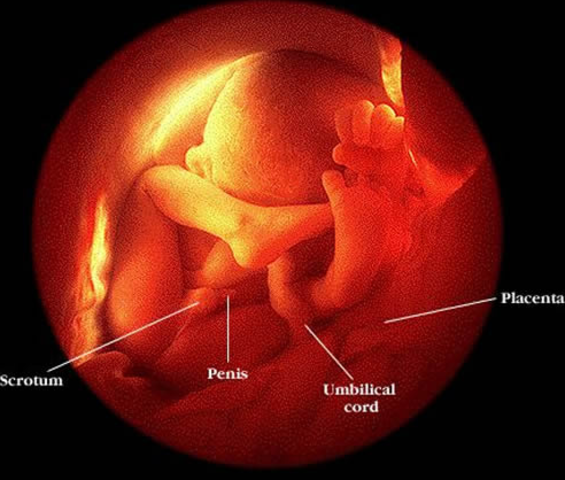

• 19 weeks

19 weeks

Your baby's sensory development is exploding! Her brain is designating specialized areas for smell, taste, hearing, vision, and touch. Some research suggests that she may be able to hear your voice now, so don't be shy about reading aloud, talking to her, or singing a happy tune if the mood strikes you. Your baby weighs about 8 1/2 ounces and measures 6 inches, head to bottom